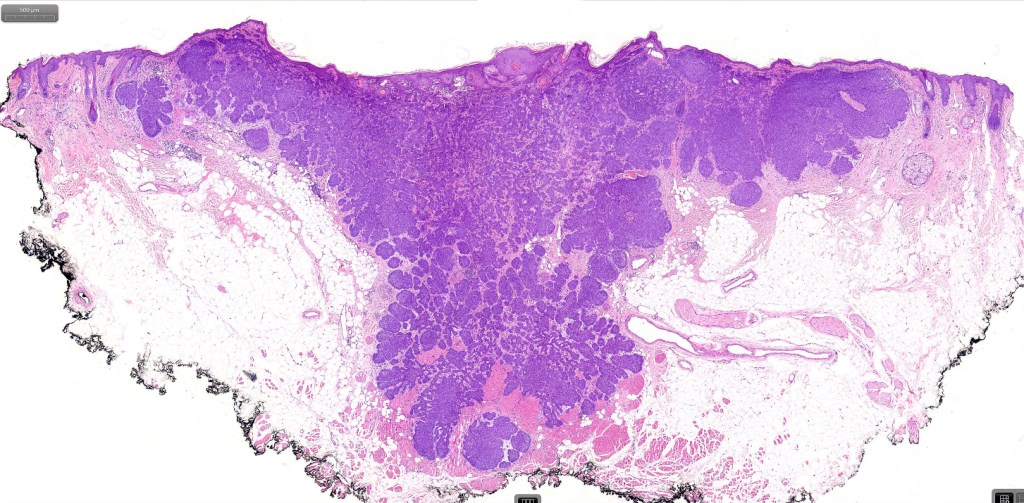

•Both epithelial & fibrous stromal components

•The tumor commonly arises from the epidermis

•A wide variety of histological variants are possible including nodular, nodulocystic, ulcerative, superficial, micronodular, infiltrating/infiltrative, keratotic, basosquamous, pigmented, morpheaform, keloidal, clear-cell, signet-ring cell & granular cell variants, BCC with monster cells, BCC with metaplastic features, BCC with matricial differentiation, basomelanocytic tumor (see separate blog), BCC with thickened basement membrane, BCC with carcinoid-like nuclear palisading & these are illustrated below